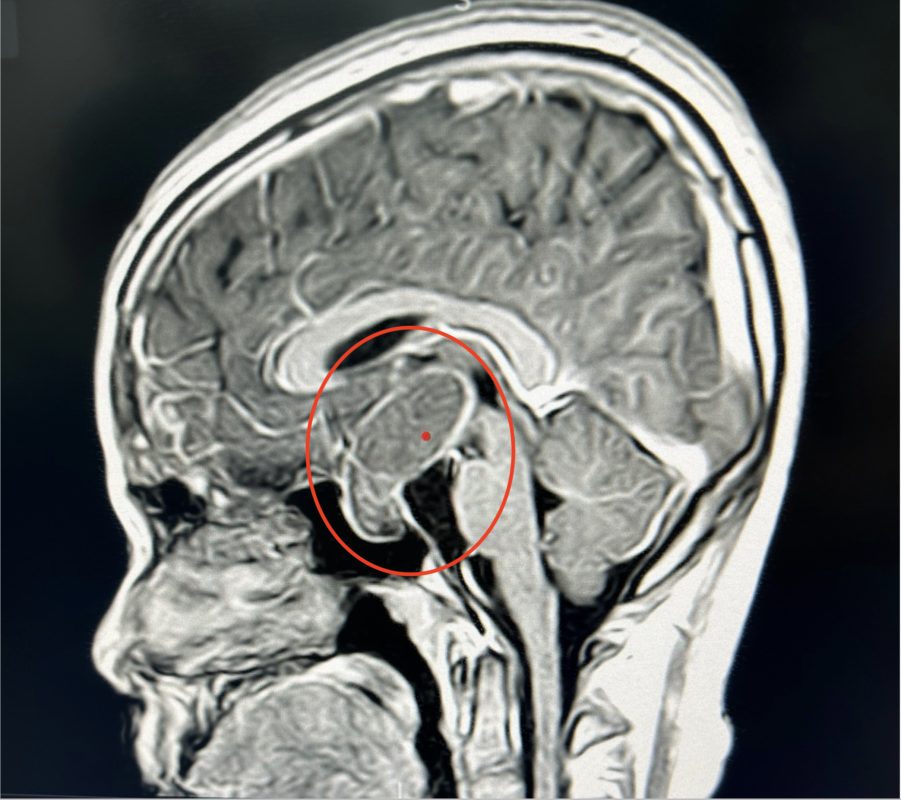

ハノイでの症例です。頭蓋咽頭腫という小児と中年に多い腫瘍で、下垂体というホルモンを分泌する器官近くに発生します。なので小児の場合、ホルモン異常や、発達障害などで発見されるケースが多く、ほぼ良性の腫瘍なので、全摘出すれば根治することが見込めます。この症例は小児の再発症例で、現地のドクターと相談し、interhemispheric approachにて視交叉前方より全摘出しました。